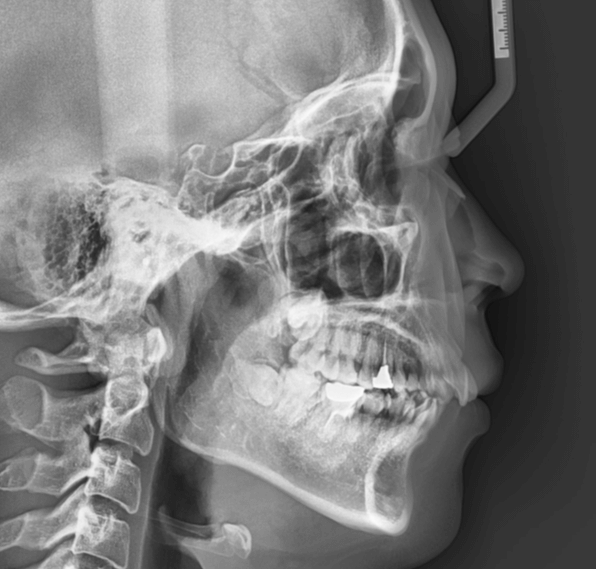

| 年齢・性別 | 25歳女性 |

|---|---|

| 主訴 | 前歯の歯並びの乱れ(叢生)を気にされて来院された25歳女性。咬み合わせや審美的な改善を希望されていました。 |

| 治療期間・回数 | 4年5ヶ月・30回 |

| 費用 | 1100,000円(税別) |